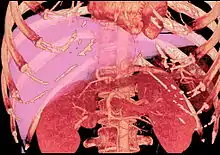

Left lobe liver tumor

After resection of left lobe liver tumor